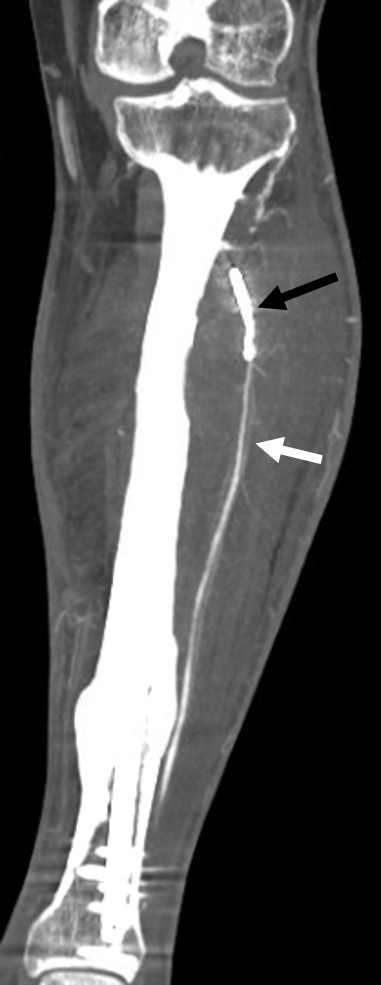

Figure 4: (a and b) Angiogram after selective catheterization of the left anterior tibial artery (ATA) demonstrates contrast filling of pseudoaneurysm (white arrows) and the origin at the proximal ATA (black arrow) near the screw. After coil embolization (b), the angiogram shows no contrast filling into the pseudoaneurysm cavity (black arrows), consistent with the successful cessation of blood flow into the pseudoaneurysm cavity. Following embolization, a left leg incision was made over the most prominent area of fluctuance, and the large hematoma cavity was entered. Suction and manual evacuation were used to remove approximately 250 cc of old thrombus along with the pseudoaneurysm capsule. A closed suction drain was placed in the evacuated cavity, and the incision was closed with interrupted nylon sutures. Sterile dressings were applied. The post-operative course was uncomplicated, and the patient recovered well. At the 3-month follow-up, CTA demonstrated post-procedural changes consistent with embolization of the ATA pseudoaneurysm. The distal ATA remained patent, with no evidence of recurrence. The aneurysm neck was successfully sealed, and there was a reduction in the size of the aneurysm sac (Fig. 5).

Figure 5: Coronal computed tomography angiography shows embolization of the anterior tibial artery pseudoaneurysm (black arrow) and patent distal anterior tibial artery (white arrow) without extravasation to suggest recurrence of the pseudoaneurysm.